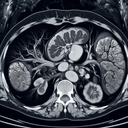

МРТ нирок

Магнітно-резонансна томографія (МРТ) нирок — це безпечний і неінвазивний метод обстеження, який використовує магнітне поле та радіохвилі для отримання детальних зображень нирок. Ось як підготуватись до процедури: 1. **Консультація з лікарем**: Перед обстеженням повідомте лікаря про наявність алергій, вагітності, клаустрофобії або встановлених медичних імплантів (наприклад, кардіостимуляторів)...